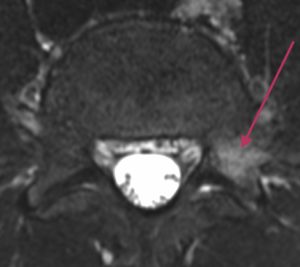

Lannerangan poikkileikkaus 1

Lannerangan aksiaalikuva (poikkileikkaus).

Tarkka diagnostiikka

Magneettikuvauksen avulla voidaan nähdä selkäydinkanavan tilavuus ja hermojuurten vapaa tila. Poikkileikkauskuvista (aksiaalitaso) voidaan luotettavasti todeta mahdolliset hermopinnetilat, joita esimerkiksi välilevyn pullistuma voi aiheuttaa.